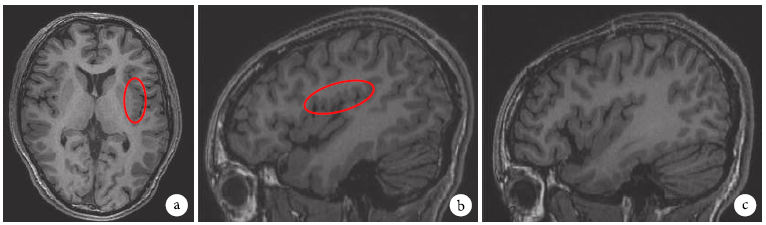

③正电子发射计算机断层扫描(PETCT)提示:左侧岛叶及周围的额叶、颞叶、顶叶局部代谢较右侧弥漫性减低(图4)。

1567899647546066.png

图4 PET-MRI左侧岛叶后部及额顶盖多小脑回局限性低代谢。a.轴位,b.左侧岛叶岛盖,c.右侧岛叶岛盖